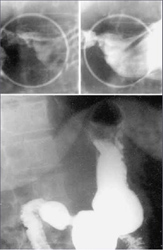

Современные технологии в медицине: рентгенодиагностика заболеваний желудка